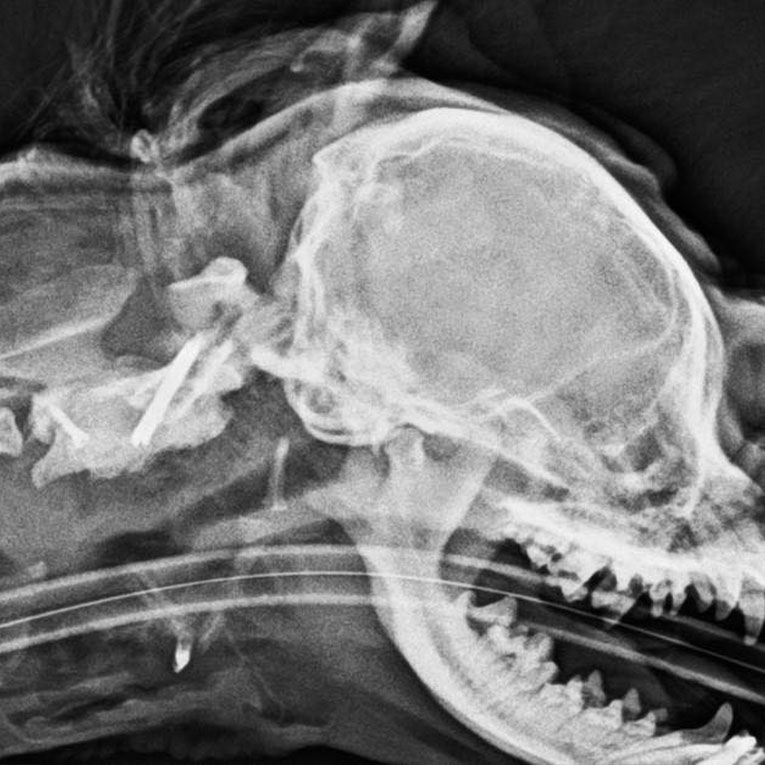

At Veterinarium, a Pekingese dog, Bubu, was diagnosed with atlanto-axial subluxation, a condition characterized by instability between the first and second cervical vertebrae (C1-C2), which can lead to spinal cord compression and subsequent neurological dysfunction.

For accurate diagnosis, computed tomography (CT) was performed at the Vet CT facility located on the Kakha Bendukidze Campus. Based on the imaging findings, the diagnosis of atlanto-axial subluxation was confirmed by Veterinarium’s Head Veterinarian, Dr. Lasha-Giorgi Japaridze.

Given the severity of the condition, surgical stabilization was undertaken. Fixation of the atlanto-axial joint was achieved using two transarticular threaded pins placed across the C1-C2 articulation. Additionally, two screws were inserted into the cranial and caudal aspects of the axis (C2). Bone cement was applied in combination with the pins and screws to reinforce fixation.

The post is accompanied by a computed tomography (CT) image.